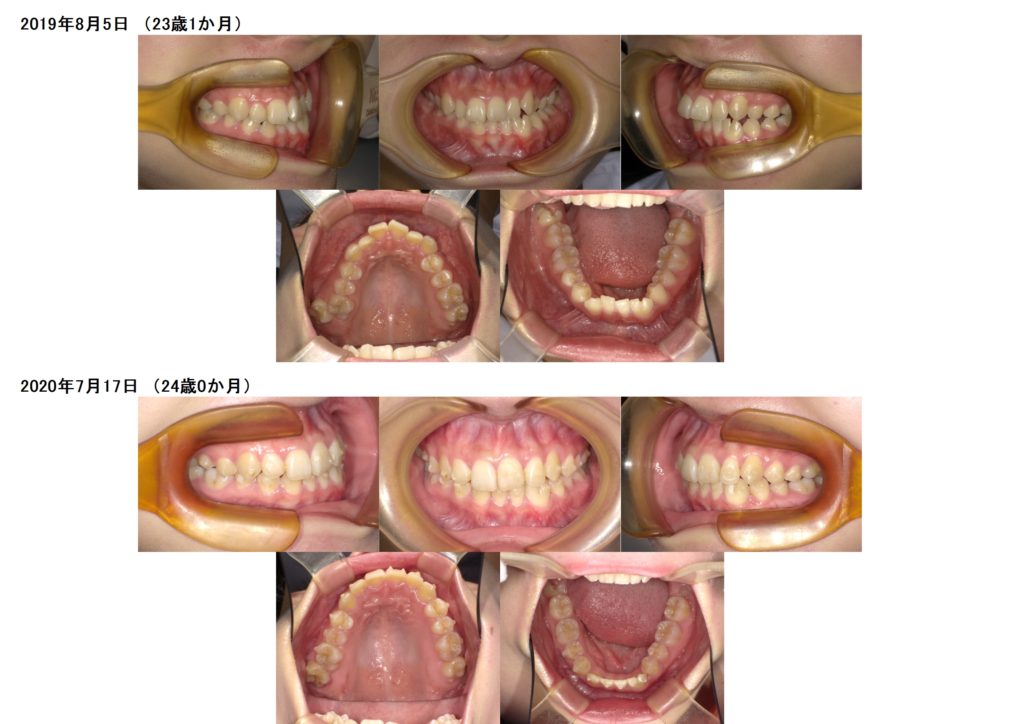

↑上が初診時のお口の中になります。

左下の部分が癒合歯になります。

少しだけ歯が大きいのです。

マウスピースを使用し、治療を開始しました。

上下の顎のアーチを整え、歯が並ぶスペースを確保します。